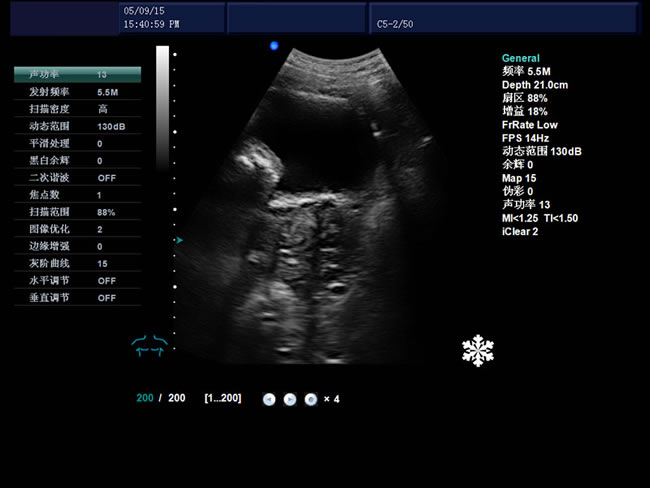

S9 彩色多普勒獸用超聲診斷儀

• S9彩色多普勒獸用超聲診斷儀是徐州市大為電子設備有限公司推出的一款全新的彩色超聲診斷儀器。

• 臨床應用